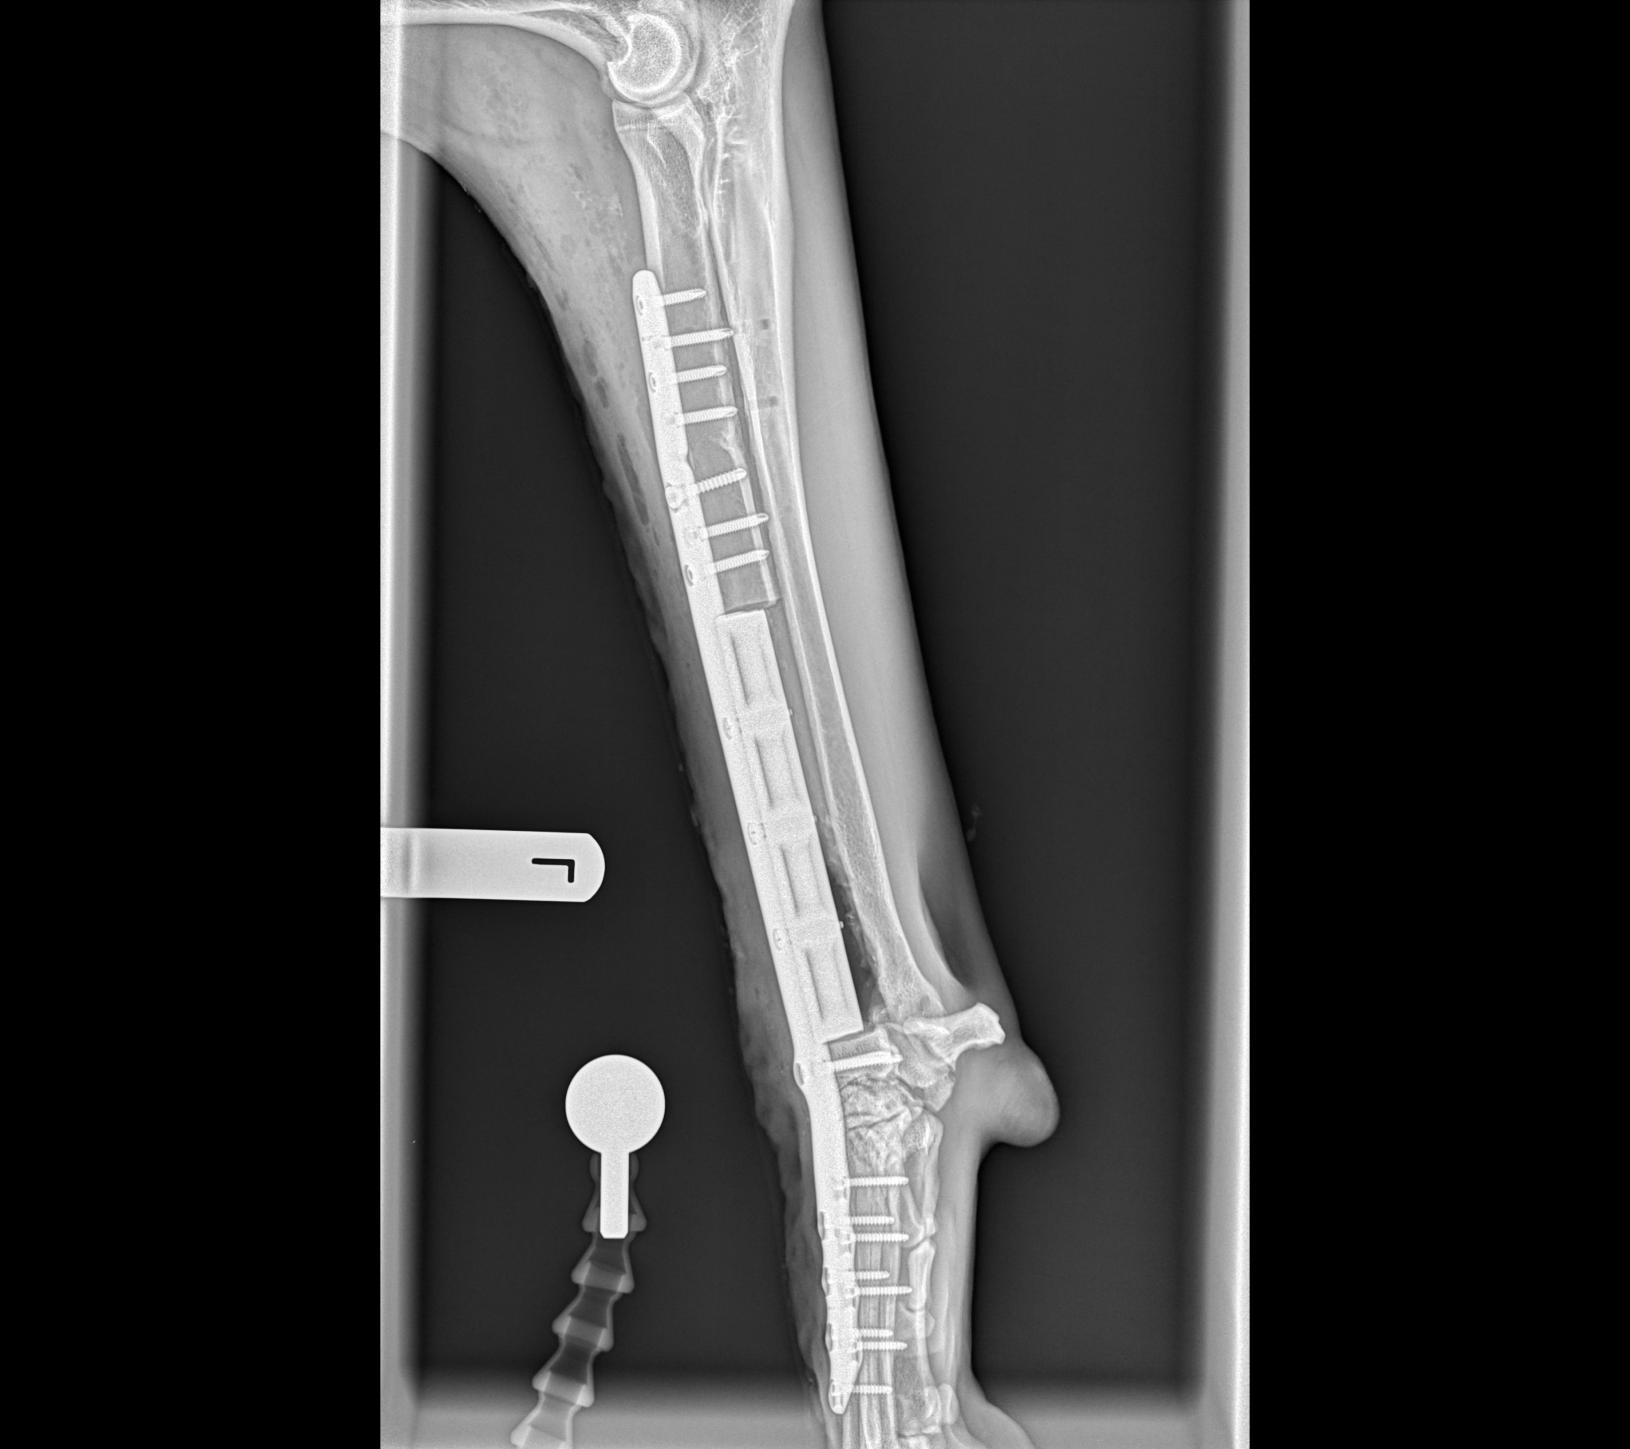

Su aplicación principal es en pacientes con neoplasias (tumores) óseas, como es en la mayoría de casos el osteosarcoma. Ante esta situación tradicionalmente era necesario llevar a cabo una amputación radical del miembro afectado. Actualmente gracias a técnicas de salvación de miembro, siempre y cuando el estado de salud general del paciente lo permita, es posible la resección quirúrgica del tumor y la reconstrucción de la extremidad afectada empleando diferentes prótesis anatómicas que ayudarán a restaurar la estructura y la función del miembro afectado.